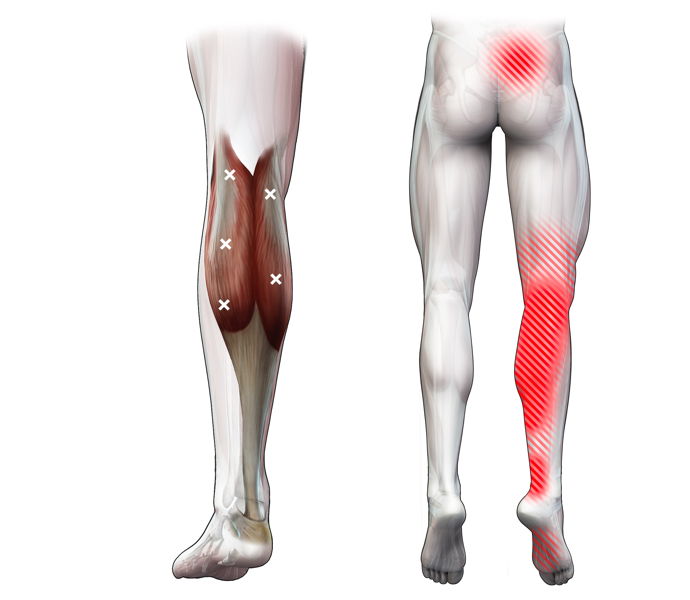

Spieren (Nederlands)

Spieren (nederlands)

Spieren (Latijn)

Spieren (latijn)

Trefwoorden

Trefwoorden